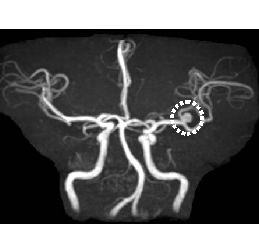

• MRA画像

左内頸動脈狭窄

脳動脈瘤